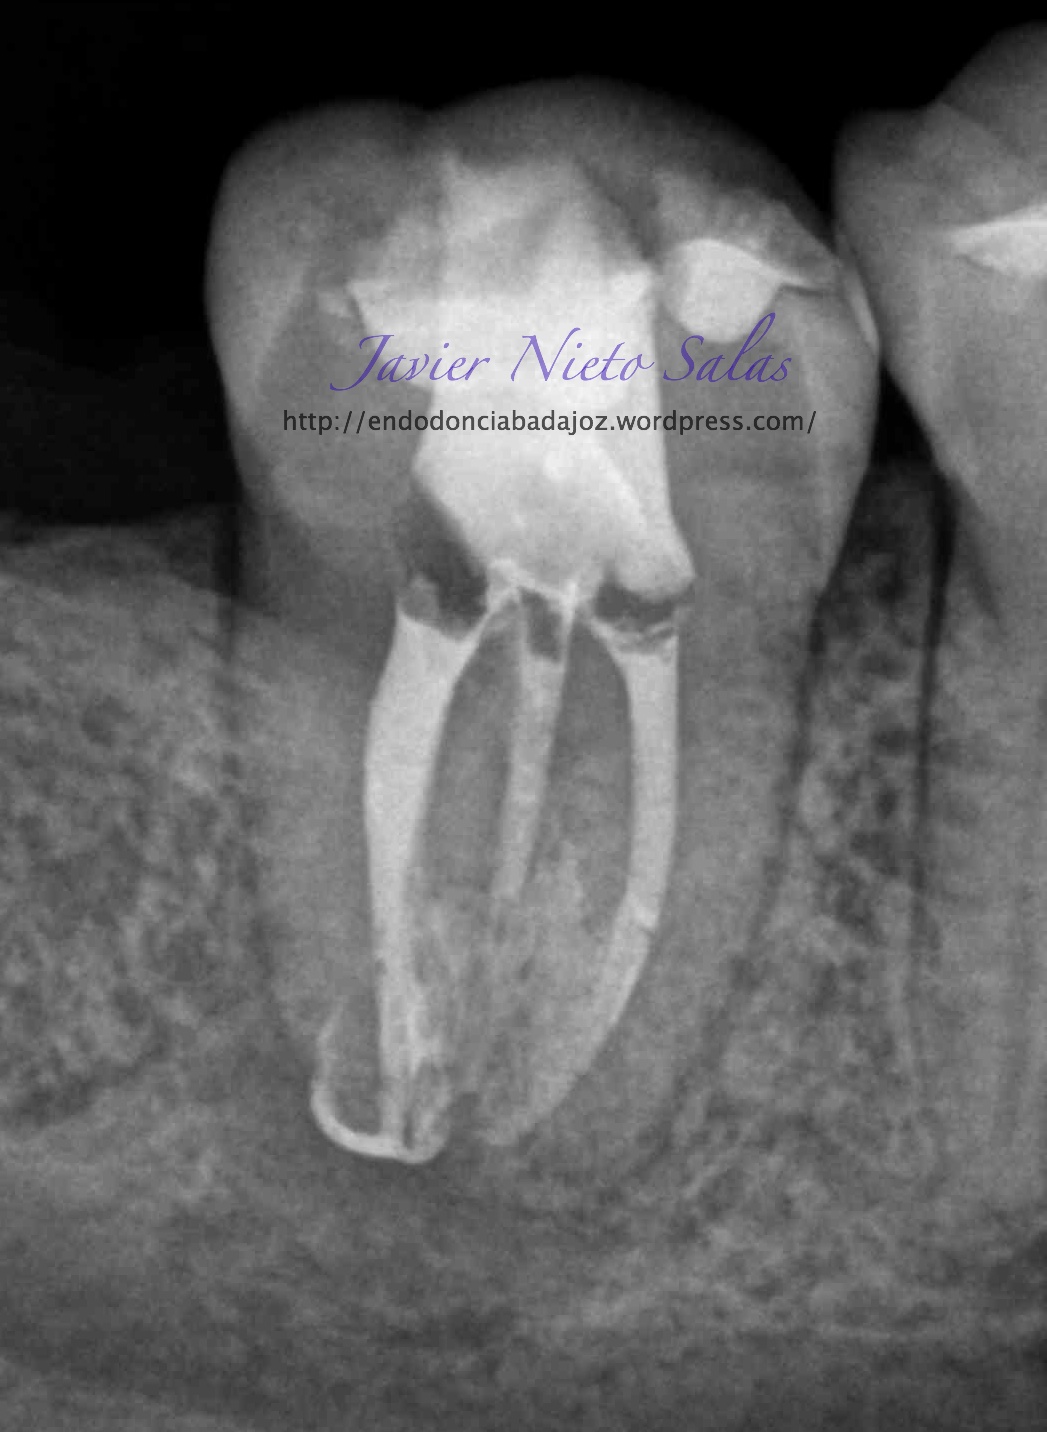

En el siguiente caso:

Se trata de una caso con una clasificación Tipo IIIb por el método de Min, ya pudimos sospechar que se trataba de un conducto en C:

Así podemos modificar nuestra técnica de obturación sabiendo que se trata de un sistema de conductos complicados